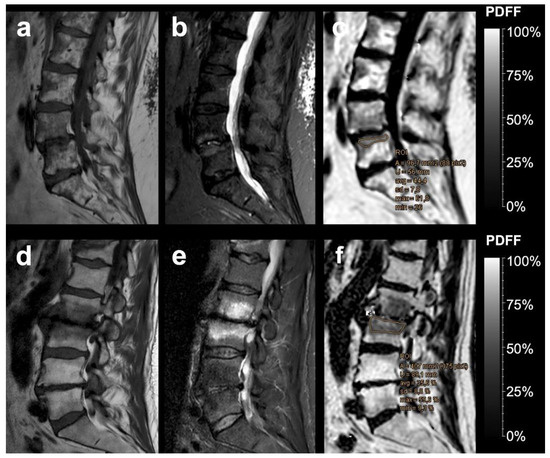

| PDFF | % | 35.29 | 17.15 | 4.28 | 3.12 | <0.001 * |

| PDFFratio | 0.67 | 0.37 | 0.093 | 0.059 | <0.001 * | |